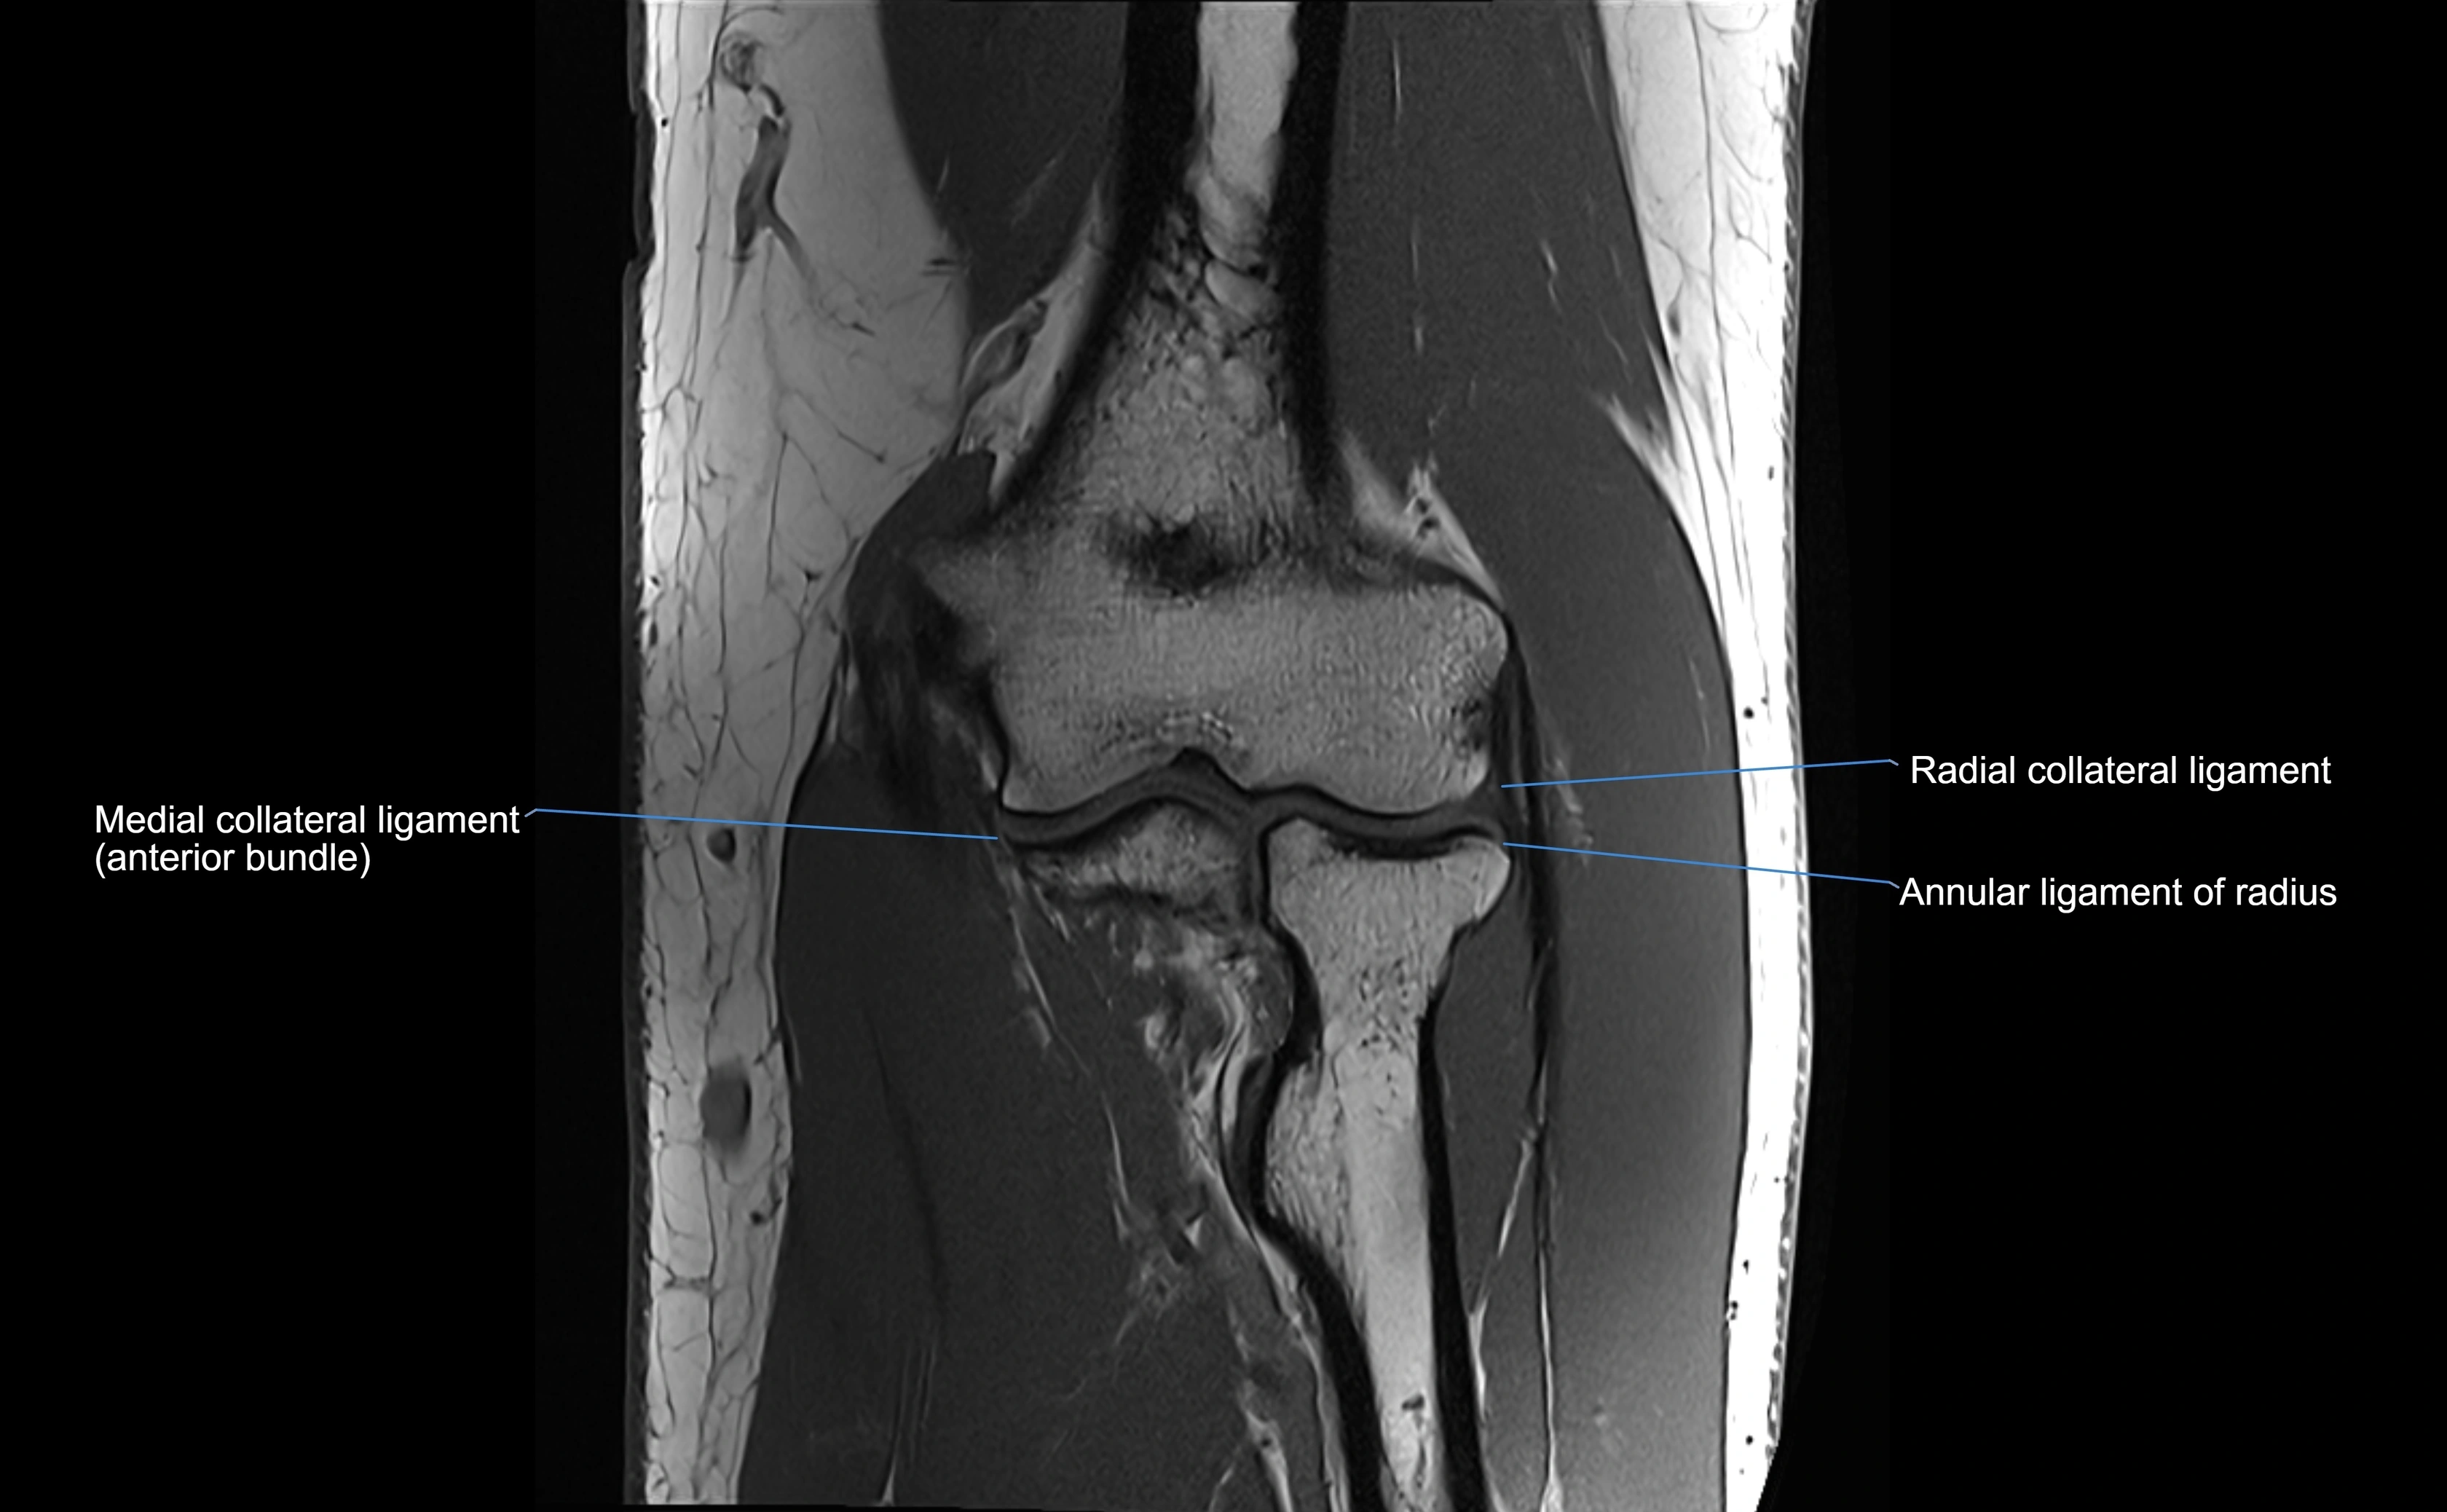

MRI Appearance

T1-weighted images:

• Ligament: low signal intensity (dark), appearing as a continuous band around the radial head.

• Adjacent fat and marrow: bright, creating contrast with the ligament.

• Thickening or disruption indicates injury or fibrosis.

• Joint capsule and synovium seen as thin low-signal lines contiguous with ligament margins.

T2-weighted images:

• Ligament: low signal (dark) with clear delineation from joint fluid.

• Fluid or edema: bright hyperintense, separating or surrounding the ligament in partial tears.

• Complete tear: discontinuity or non-visualization of ligament fibers, often with joint effusion.

Proton Density Fat-Saturated (PD FS):

• Normal: dark, well-defined band outlining the radial head.

• Partial tear: irregular or bright hyperintense signal within or adjacent to ligament fibers.

• Joint effusion and reactive synovitis appear bright and are well visualized.

MRI Arthrogram Appearance

• Contrast outlines the proximal radioulnar joint and radial head recess.

• Normal ligament appears as a dark ring surrounding the radial head, containing the injected contrast within the joint cavity.

• Partial tear: contrast extends along the ligament or beneath its fibers.

• Complete tear or subluxation: contrast extravasates around the radial head or ulna, indicating discontinuity.

• Detects capsular defects, instability, or synovial invagination with high sensitivity.

MRI images

image